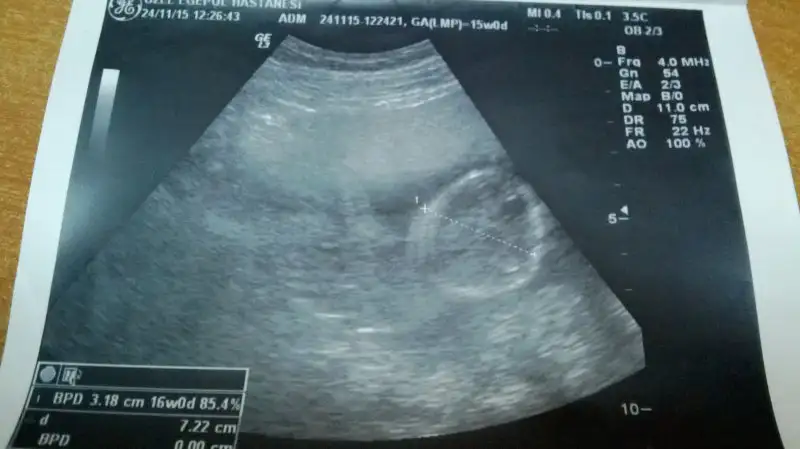

Buda 16 haftalıkken ki görüntüsü kuzumun